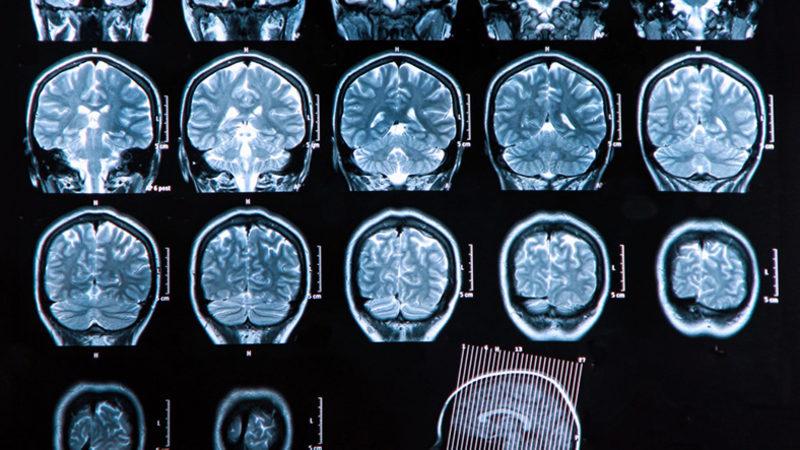

Pennsylvania Üniversitesi’nde yapılan yeni çalışmada üç kıtadan şizofreni hastalarının 300’den fazla MRI beyin taraması HYDRA adı verilen yeni bir makine öğrenme yöntemi ile analiz edildi. Makine öğrenme ile yapılan analiz sonuçları, bazı beyin bölgelerinde düşük miktarda gri madde bulunduğu yönündeki görüşlere meydan okuyor.

Yapılan analizde, şizofreni hastalarının yaklaşık yüzde 40’ının nispeten normal gri madde hacimleri gösterirken, şizofreni hastalarının önemli bir miktarı sağlıklı kontrol grubunun beyin taramalarına kıyasla, striatum adı verilen orta beyin bölgesinde gri maddede küçük de olsa artış gösterdi.